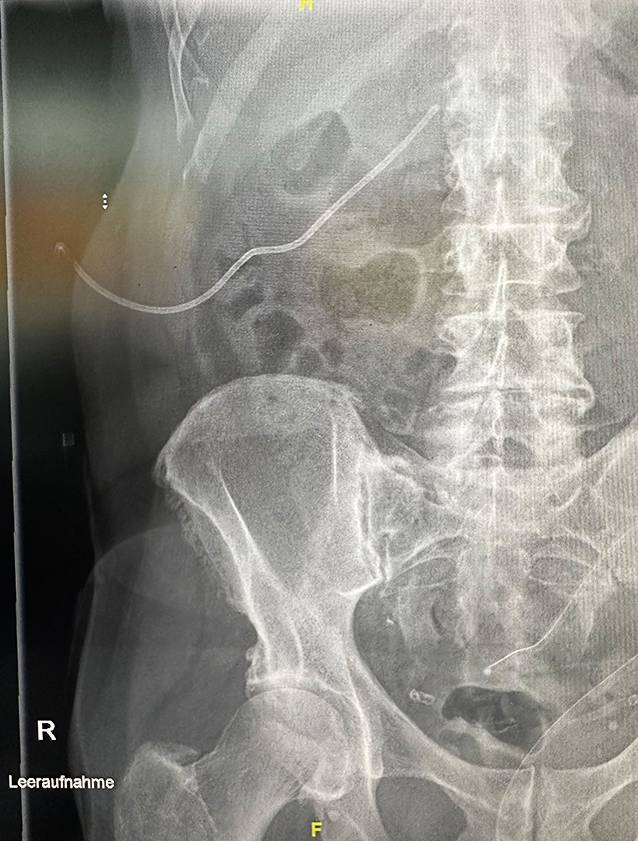

[Presentation of a new pre-emptive endoscopic treatment concept in duodenal interventions exemplified by an iatrogenic duodenal perforation after percutaneous transrenal nephrostomy. German version].